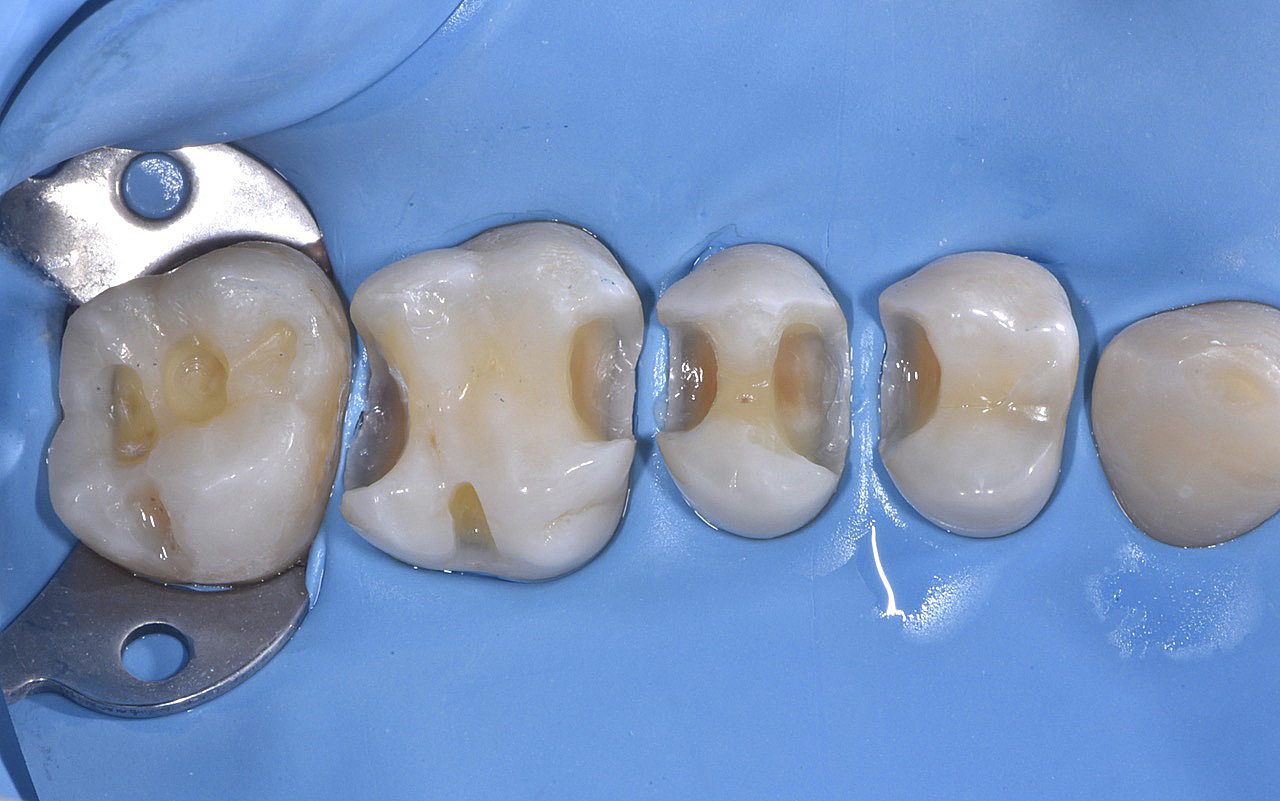

Vengono utilizzati 2 tipi di provvisori: il primo, cementato ai denti vicini, viene utilizzato dal momento dell’estrazione del dente fino ad impianto osteointegrato (circa 6 mesi); il secondo, avvitato direttamente all’impianto, ha una funzione di prova estetica ma soprattutto di guida per la maturazione dei tessuti gengivali peri-implantari portandoli verso la maturazione completa prima di posizionare la corona finale in disilicato di litio.